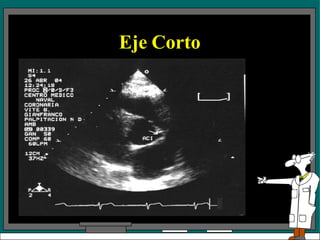

Eje Corto

• El espacio intercostal es el mismo para los

planos 2, 3 y 4.

• El examen en el plano 1 requiere mover el

transductor a un espacio intercostal inferior